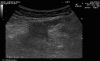

Figure 13.

Ultrasound image of spigelian hernia. Defect is shown (between the arrows).